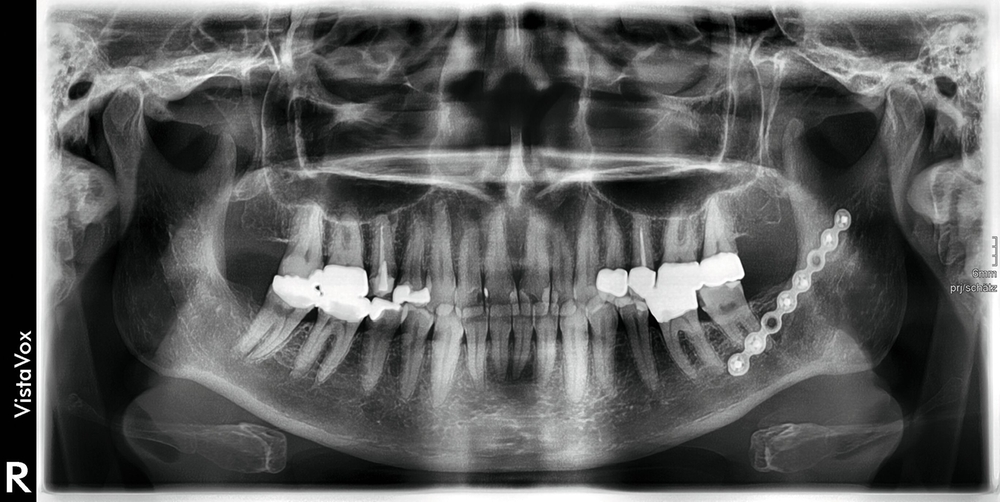

Der postoperative Verlauf gestaltete sich komplikationslos. Die radiologische Kontrolle ergab keinen Anhalt für ein Residuum der Raumforderung oder für eine Fraktur des Unterkiefers. Die Osteosyntheseplatte war suffizient anliegend (Abbildungen 4a und 4b). Klinisch bestand eine geringgradige Hypästhesie im Versorgungsgebiet des Nervus alveolaris inferior. Die Patientin konnte am zweiten postoperativen Tag bei gutem Allgemeinzustand entlassen werden.

Eine Kontrolluntersuchung zwei Monate postoperativ zeigte einen unauffälligen Heilungsverlauf. Die Hypästhesie des linken Nervus alveolaris inferior war im Wärme-/Kältetest, durchgeführt mit einem NeuroSensory Analyzer (TSA-Test), noch objektivierbar, aber deutlich regredient (Abbildung 4c). Eine weitere röntgenologische Untersuchung sieben Monate nach Operation zeigte eine zunehmende Verknöcherung der Resektionshöhle ohne Rezidivverdacht. Der intraorale Befund war reizfrei und die Sensibilität nahezu vollständig wiederhergestellt (Abbildung 5).